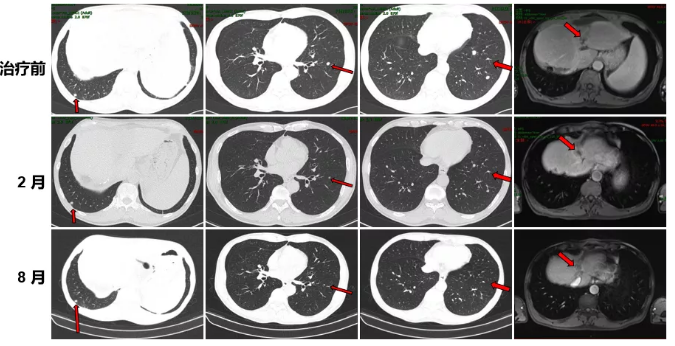

2017.12 复查提示CEA 16.16 ng/ml,CA 125 111.2 u/ml,肺部CT提示双肺及叶间裂胸膜处多发小结节。

肺部CT检查

2017.12.20-2018.03.05行4周期FOLFOX4联合贝伐珠单抗治疗。

化疗前后病灶变化情况

治疗前后病灶变化情况